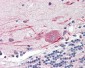

ApplicationIHC-P

ReactivityH, Pr, Pig, B, D, Hs, Sh, (M)

AccessionO00482